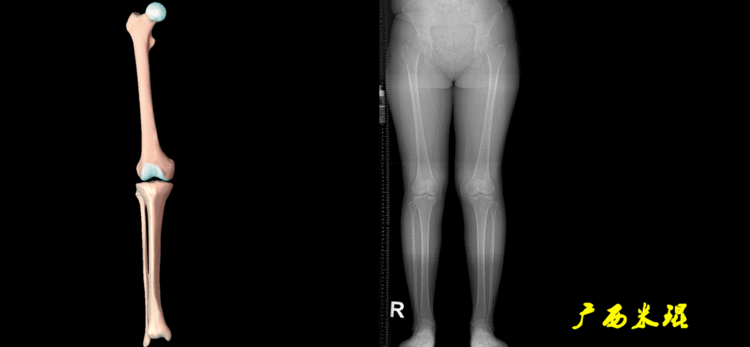

下肢力线及相关角度测量的前提是必须拍摄标准的站立位也就是负重位的下肢全长片。目前这样的照片都是放射科的技师在电脑上拼接出来的,大部分医院的DR都能够做到这一点。

患者直立于摄影架上,后背贴近摄影架,双手自然下垂,膝关节尽量伸直,足部与双肩同宽,要求投照时双髌骨朝正前方,通常患者双足尖应平行向前即可。

提醒一下大家,拍摄过程中应避免下肢的外旋和内旋。如果有一侧肢体短缩时,投照应当用脚垫垫高短缩肢体,使骨盆保持水平,这样下肢短缩测量才精确。如果有肢体旋转畸形时,还是以髌骨朝前为标准,虽然此时双足可能不能保持平行。

下肢全长片的基本要求

无论如何,拍摄出来的下肢全长片必须包含髋关节中心、膝关节中心及踝关节中心,否则对临床是无用的。有了一张下肢的全长照片,我们需要确定下肢关节的中心点,通过中心点画出下肢的各种轴线,然后利用轴线与关节线的相交得出各种所需要的角度。